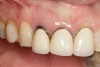

Fig 4. Radiograph showing root fracture and apical lesion of the tooth (No. 7).

Figure 4